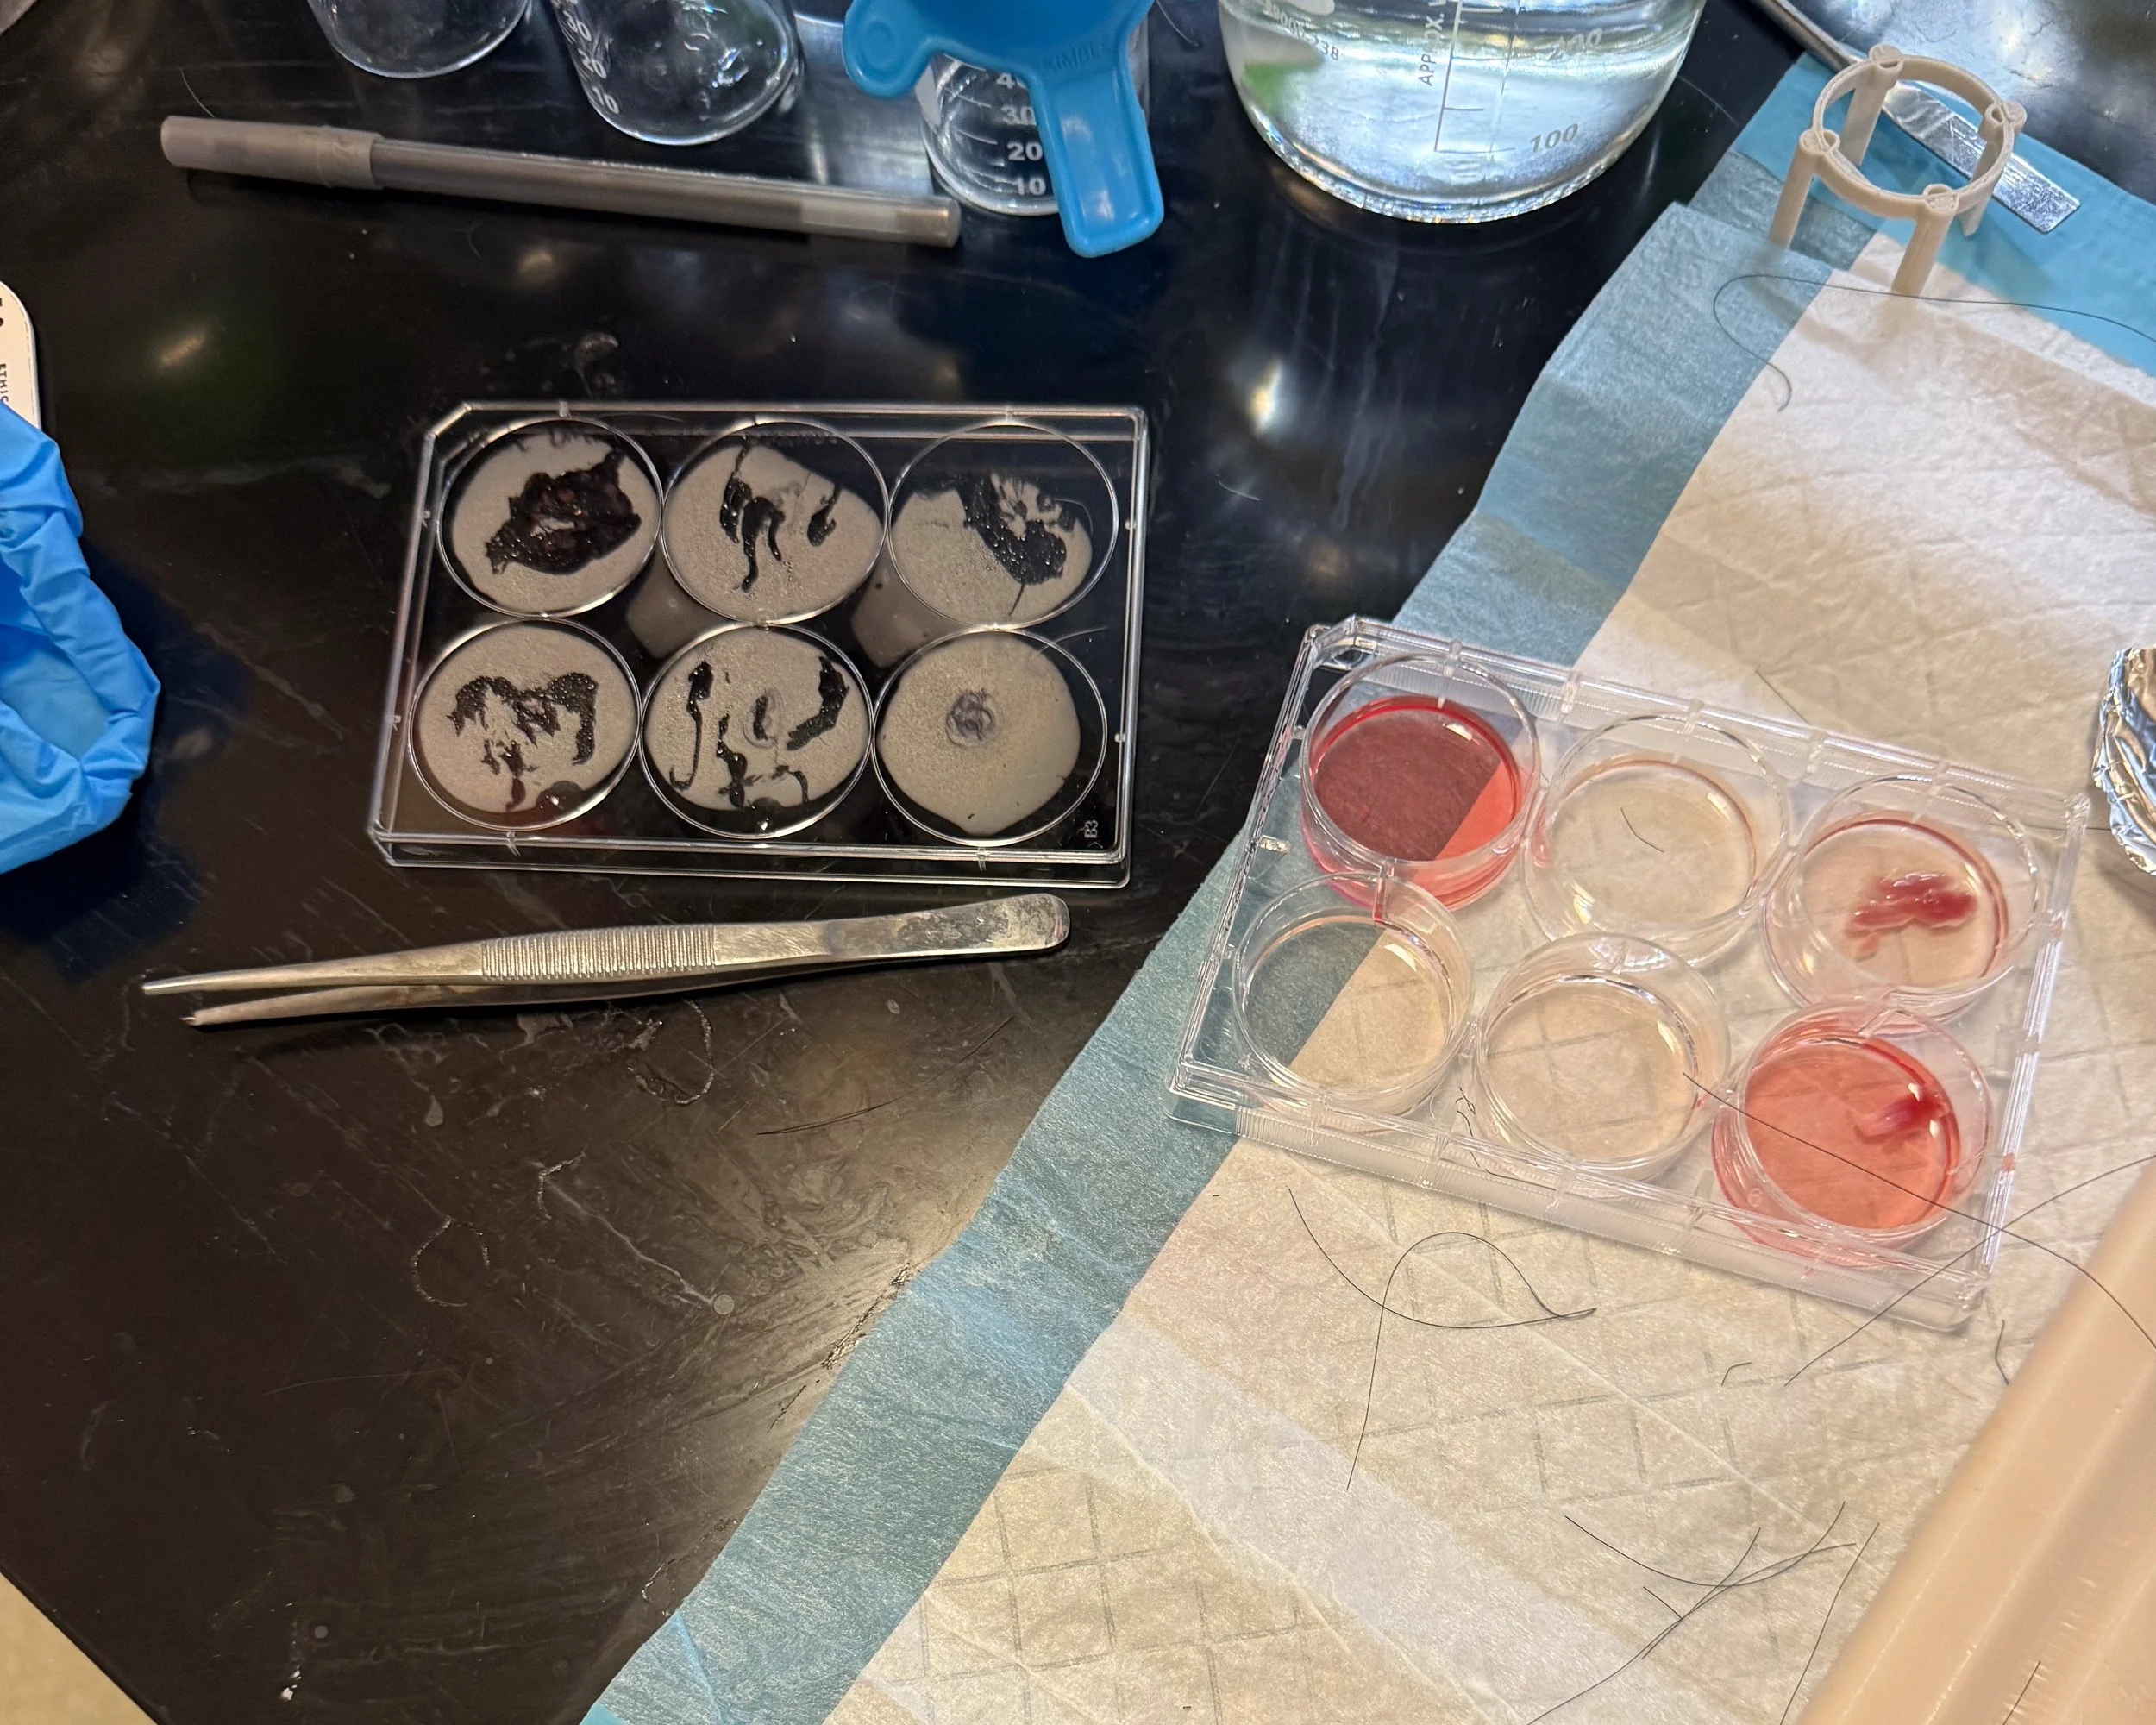

Develop: DMM is being tested on laboratory models to demonstrate effectiveness and comparisons to off-the-shelf products on the market.

Sustain: Testing has shown success in new muscle growth after two months, with potential indications that include supraspinatus muscle and tendon damage, stress and pelvic floor issues, and patch augmentation or interposition grafting.

Gallery: DMM in development at the Sarcogenics lab

Remove cells, keep structure

Donor muscle tissue is processed to strip away all living cells, leaving behind the extracellular matrix — a natural scaffold made of proteins like collagen, laminin, and fibronectin.